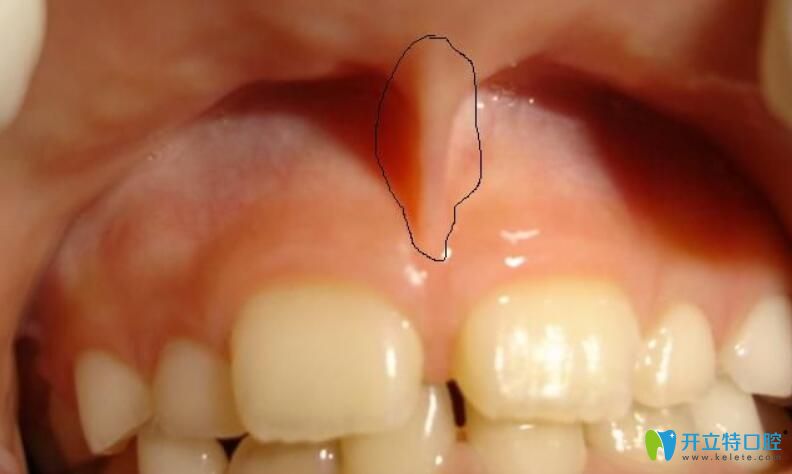

10、多生牙

任何牙位都可能萌生多生牙,不過多生牙較長在的位置是上門牙間有多余,多生牙多為畸形牙,它們占據(jù)了正常牙的位置,會致使這些正常的牙齒出現(xiàn)錯位或萌出障礙。

多生牙